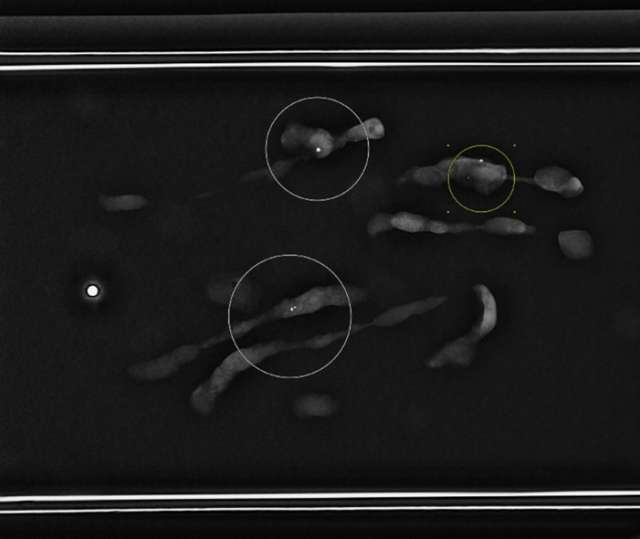

• Radiologist confirms adequate tissue sampling (Figure 5).

Figure 5. Specimen radiograph demonstrates multiple tissue samples containing calcifications (circled).